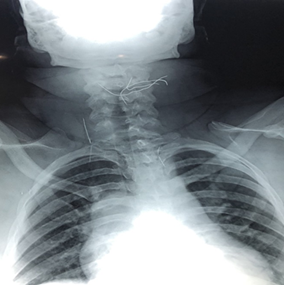

A Nasofibroscopy was performed showing no sign of

laryngeal damage. A cervico-thoracic x-ray showed multiple wires above the

thyroid cartilage, one supra-clavicular reaching the right hemithorax, and

another one intra-thoracic (Figure 1).

Figure

1: Cervicothoracic

x-ray-frontal view showing multiple cervicothoracic wires (arrow)